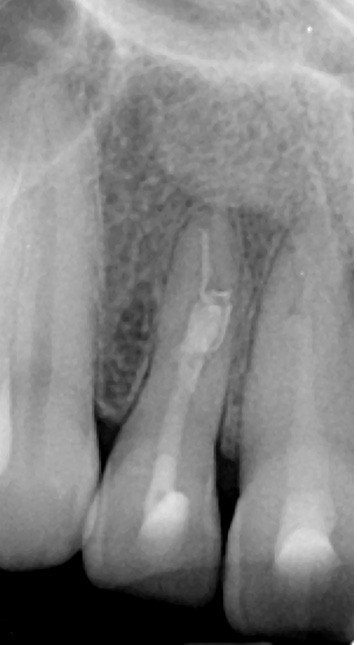

L’utilisation d’instruments en nickel titane, tels que le XP Shaper (FKG), le Vortex blue (Dentsply) ou le Profile (Dentsply), optimise la remontée des débris et s’inscrit dans cette nouvelle philosophie. En conséquence, la combinaison XP Shaper, XP Finisher et l’irrigation avec l’Er:YAG semblent optimiser nos traitements [44,45].

Le passage du laser est répété plusieurs fois, en début, au milieu et en fin de préparation. Un protocole peut alors être proposé : 40 mJ ; 20 Hz (fig. 7). L’utilisation de biocéramiques Bioroot (Septodont) ou Total Fill R (FKG) permet de sceller le système ainsi nettoyé, en assurant une action biologique de longue durée [46] (fig. 8a à c).